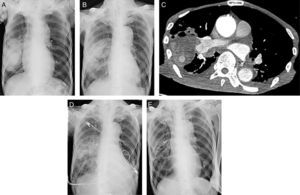

A 79-year-oldman, former-smoker, who had been suffering from wet cough and weight loss for a month, presented a tour hospital. He had been diagnosed with cerebral infarction and chronic atrial fibrillation at the age of 78 years and was receiving15mg rivaroxaban once daily. A chest X-ray showed a 12.8×7.0cm massin the right lower portion of the lung (Fig. 1A). Fiberoptic bronchoscopy showed massive purulent sputum with no obstruction of the airway, consistent with a lung abscess. Sputum culture was negative, and we empirically started antibiotic treatment with tazobactam/piperacillin. A chest X-ray performed on day 4after admission revealed slight improvement of the abscess (Fig. 1B), but hemoptysis developed 1 week later. Contrast-enhanced chest computed tomography (CT) revealed an enhanced nodule inside the abscess (Fig. 1C), suggesting PAP. The next day, because of continued hemoptysis and progressive respiratory failure, embolization of the pulmonary artery at the right A5 portion was performed with 2Interlock® detachable coils (Boston Scientific Corp), 4Hilal® embolization coils, and 1Tornado® embolization coil (Cook Medical). On day 2after embolization, contrast-enhanced chest CT revealed the disappearance of the enhanced nodule. On day 3after embolization, a chest X-ray revealed a marked decrease in the size of the abscess (Fig. 1D). One month after embolization, a chest X-ray showed almost complete resolution of the abscess (Fig. 1E). However, the patient suddenly died on day 39 after admission. The cause of death was unknown, because his family refused an autopsy.

The diameter of the lung abscess was greater than 6cm. Therefore, surgical intervention, including chest tube drainage or surgical resection, in addition to antibiotics could have been chosen to treat this abscess.1,8 Regarding surgical treatment, chest tube drainage might have been preferred because the patient's general condition did not allow surgical resection and the abscess was contiguous to the pleura. However, after admission, he complained of hemoptysis and was diagnosed with PAP, and embolization of the pulmonary artery showed remarkable improvement on chest imaging. This clinical course suggested a risk of bleeding, a life-threatening complication, with chest tube drainage. This report may have an impact on the choice of treatment for large lung abscesses.